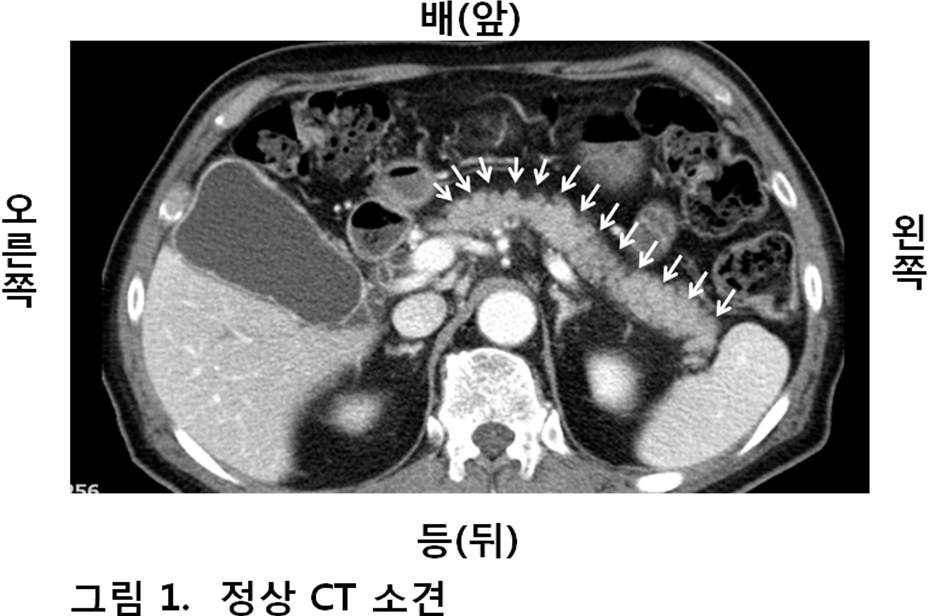

황달에 이어 췌장암의 최고 귀중한 증상은 통증으로 볼 수 있고요. 복부 통증은 가끔가다 잘 나타나는 통증이라 외면하는 경우가 넉넉한데요. 복부 중 명치 부분의 통증이 제일 비일비재하지만, 복부 어떤 부분이든 통증이 올 수 있고요. 췌장은 등과 가까워 허리 통증도 호소하는 경향이 있으나, 요통의 경우 암이 예상보다 많이 전이가 되었을 경우가 많다고 하고요.